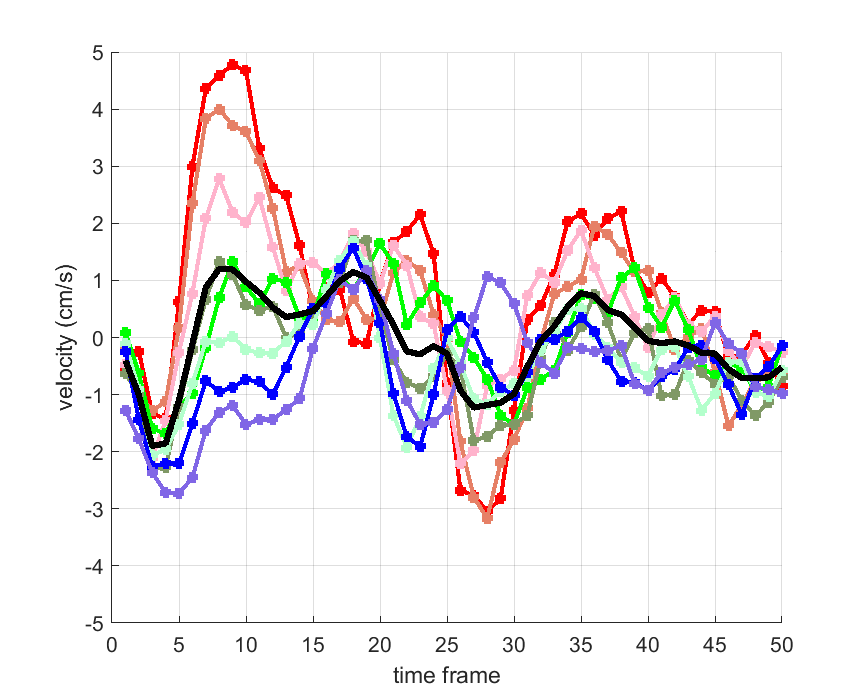

Time courses of the estimated translational component per subject, frame, slice and volume along the 3 velocity directions x, y and z are presented in Fig.6 - Fig.8.